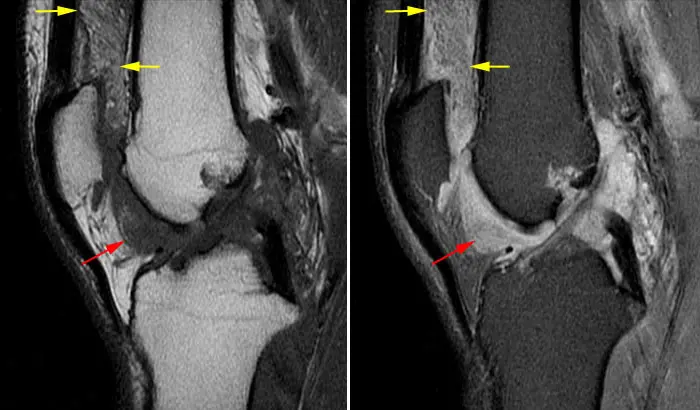

Біль в коліні може тривати довго і не мати, як здається на перший погляд, причини. Процес може тягнутися роками. Так буває при артриті, кісті Бейкера (різновид артриту коліна), при періартриті (запаленні навколосуглобових м’яких тканин) і т.ін. Причини цих запалень з’ясувати нескладно, коли провести раціональну діагностику.

Артрит колінного суглоба, кіста Бейкера (МРТ).

Хронічний артрит нерідко призводить до розвитку артрозу.